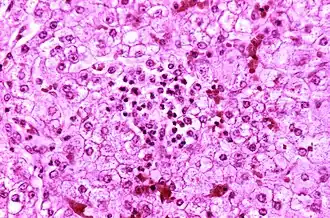

Histopathologie van syndroom van Reye van een leverpreparaat

Het syndroom ontstaat meestal wanneer iemand begint te herstellen van een virale ziekte. Het veroorzaakt een vette lever (of hepatische steatose) en ernstige encefalopathie, gepaard gaande met een zwelling van de hersenen. De lever kan zich vergroten en steviger worden. Ook het voorkomen van de nieren kan veranderen. Geelzucht komt doorgaans niet voor.